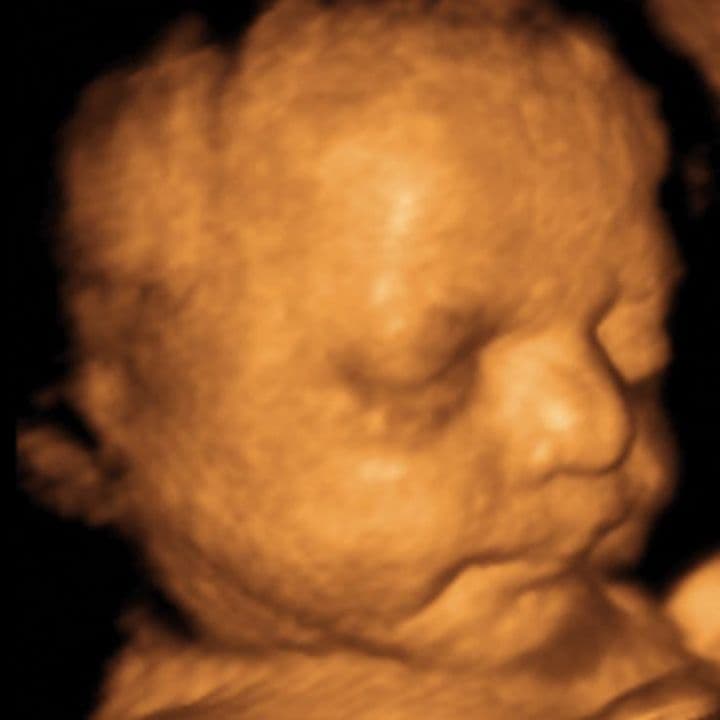

At this stage it is simply no longer possible to see the whole baby on a scan. The ultrasound scan cannot step far enough back to include the whole baby in a single view. Instead it is necessary to move the probe around, to examine one area at a time.